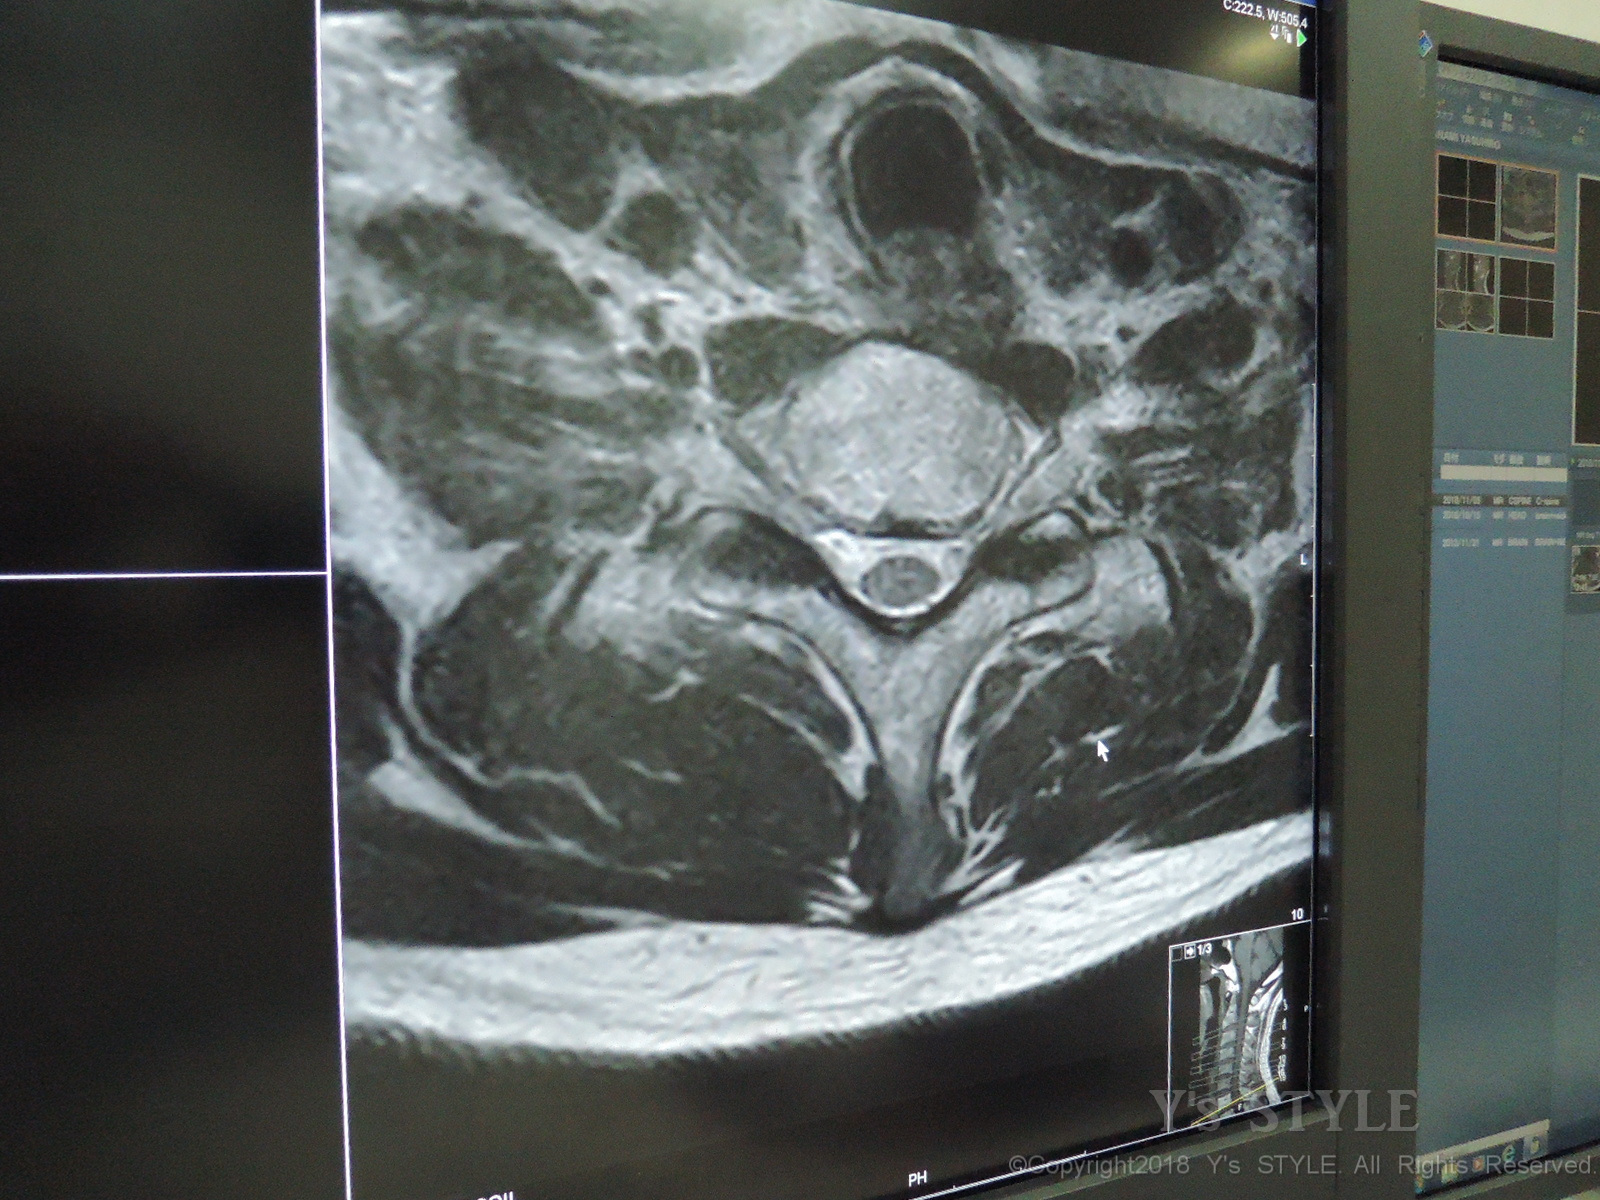

頸椎椎間板ヘルニアだそうです(;´Д`)

私の場合首を後ろ向きに反らすと左腕から指先にかけて痺れが発生します。

画像診断(MRI)って結構よく映るのね・・・(;´Д`)